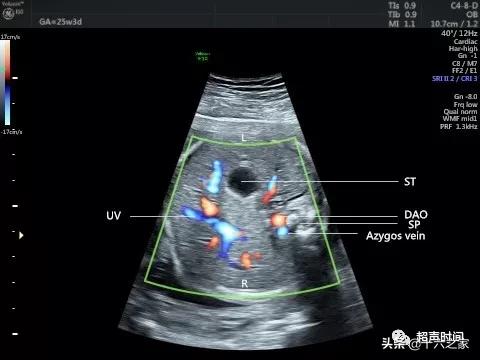

图 2 和视频 2 CDFI 示主动脉及扩张的奇静脉血流